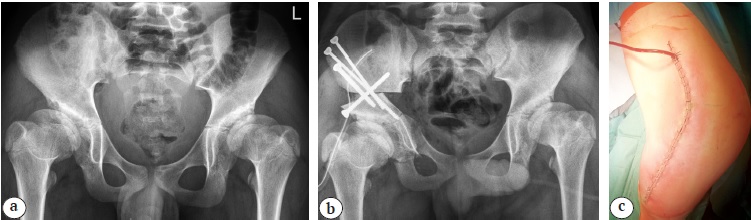

Медиальный трансаддукторный доступ и доступ «бикини». Положение пациента на операционном столе — лежа на спине. На нижней конечности в положении сгибания и разведения на стороне вмешательства выполняется поперечный разрез кожи и подкожно-жировой клетчатки в проекции сухожилия m. adductor longus длиной до 4 см. Тупо в межмышечном промежутке формируется канал до седалищной кости. После поднадкостничного выделения долотом выполняется ее периацетабулярная остеотомия. Следующим этапом производится разрез кожи и подкожно-жировой клетчатки на 1 см ниже крыла подвздошной кости вдоль паховой складки длиной до 15 см. После рассечения фасции визуализируется, выделяется на протяжении и смещается n. сutaneous femoris lateralis. В промежутке между m. tensor facia lata и m. sartorius выделяется крыло подвздошной кости с последующим рассечением его хрящевого апофиза, поднадкостичным выделением тела подвздошной кости и проведением проволочной пилы в седалищную вырезку. Дальнейшие манипуляции не имели отличий от аналогичных, выполняемых из переднебокового доступа (рис. 2).

Рис. 2. Выполнение тройной остеотомии таза из двух хирургических доступов: a — рентгенограмма пациента 16 лет с дисплазией тазобедренных суставов I степени по Crowe до операции; b — рентгенограмма после восстановления корректных соотношений между тазовым и бедренным компонентами тазобедренного сустава методом реориентирующей тройной остеотомии таза слева; c — вид хирургического доступа после ушивания